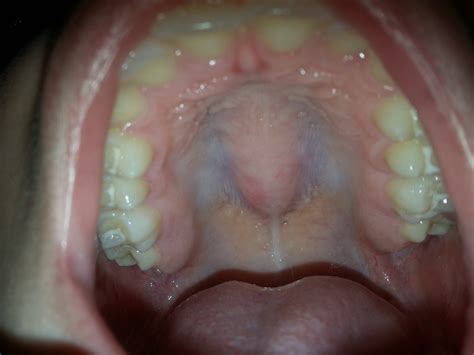

A swollen mouth palate, or oral mucosal swelling, occurs when the soft tissue on the roof of the mouth becomes inflamed and enlarged. This condition can affect anyone, regardless of age, and can be caused by a multitude of factors. The palate is a crucial part of the oral cavity, playing a significant role in speech, swallowing, and breathing. When it becomes swollen, it can disrupt these functions and cause discomfort.

Symptoms of a Swollen Mouth Palate

The symptoms of a swollen mouth palate can vary depending on the underlying cause. Common symptoms include:

• Pain or discomfort in the mouth.

• Difficulty swallowing or speaking.

• Redness or inflammation of the palate.

• Bad breath or a metallic taste in the mouth.